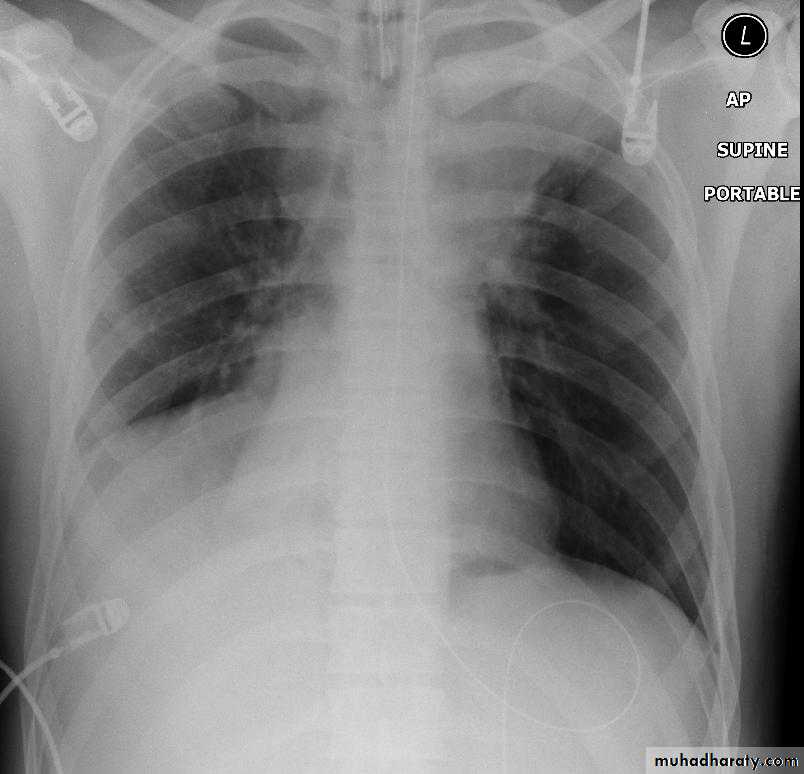

Left lower lobe collapse has distinctive features, and can be readily identified on frontal chest radiographs, provided attention is paid to the normal cardiomediastinal contours. The shadow cast by the heart does however make it harder to see than the right lower lobe collapse

Radiographic features

Left lower lobe collapseis readily identified in a well penetrated film of a patient with normal sized heart, but can be challenging in the typical patient with collapse, namely unwell patients, with portable (AP) often under-penetrated films, often with concomitant cardiomegaly. Features to be observed include :

triangular opacity in the posteromedial aspect of the left lung

edge of collapsed lung may create a 'double cardiac contour'

left hilum will be depressed

loss of the normal left hemidaphgragmatic outline

loss of the outline of the descending aorta

Non-specific signs indicating left sided atelectasis are usually also be present including:

elevation of the hemidiaphragm

crowding of the left sided ribs

shift of the mediastinum to the left

LT L L collapse